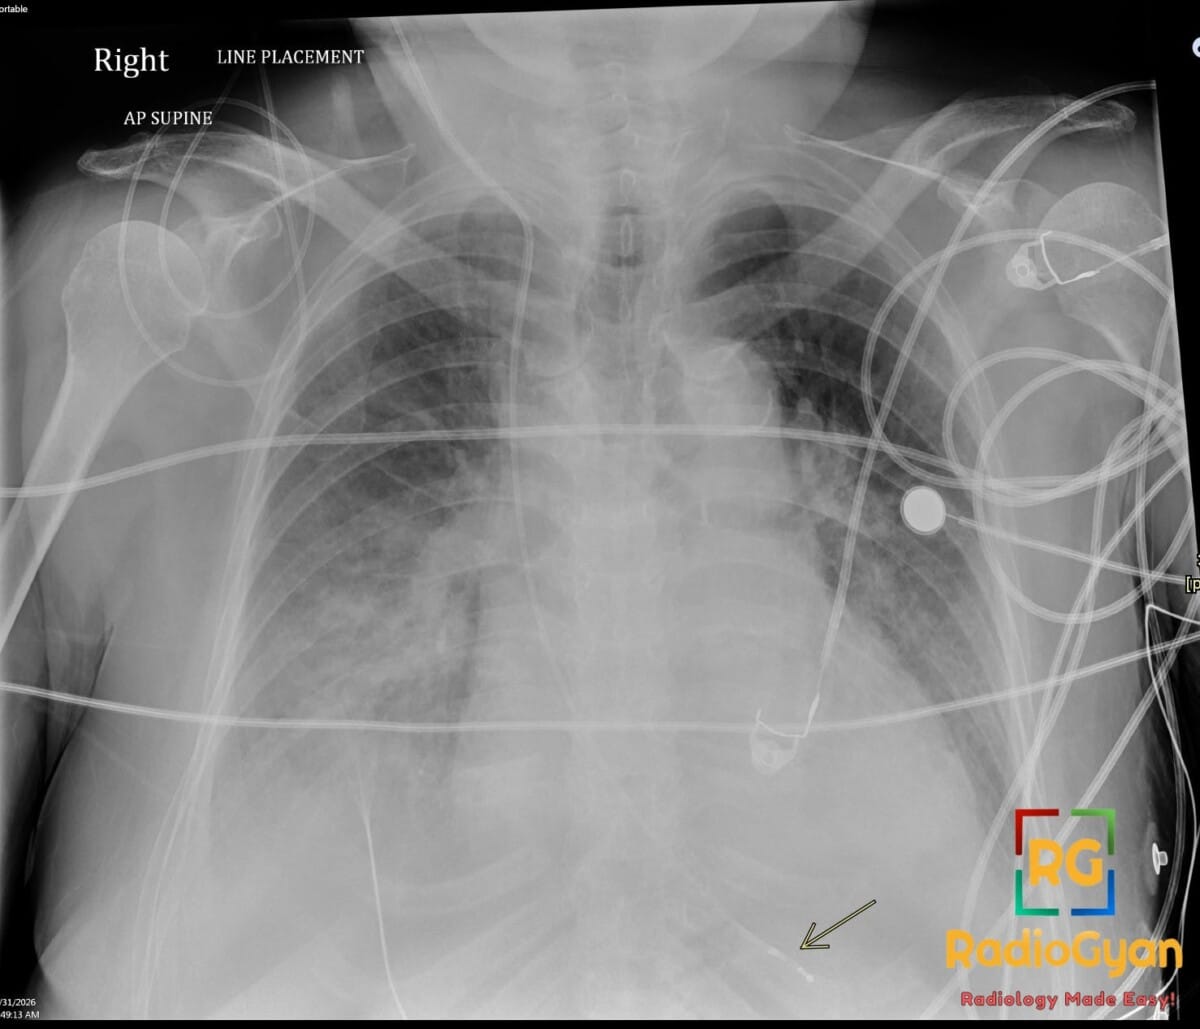

72 yr male with hemodynamically unstable bradycardia and a portable chest radiograph to evaluate device placement.

Diagnosis: Right Internal Jugular Temporary Transvenous Pacemaker

- Radiograph: Shows a radiopaque lead entering via the right internal jugular vein, traveling through the right atrium, and terminating at the right ventricular apex; must be monitored for kinks, fractures, or malposition.

- On a frontal radiograph, the lead tip should be positioned at the apex of the right ventricle, appearing to the left of the spine.